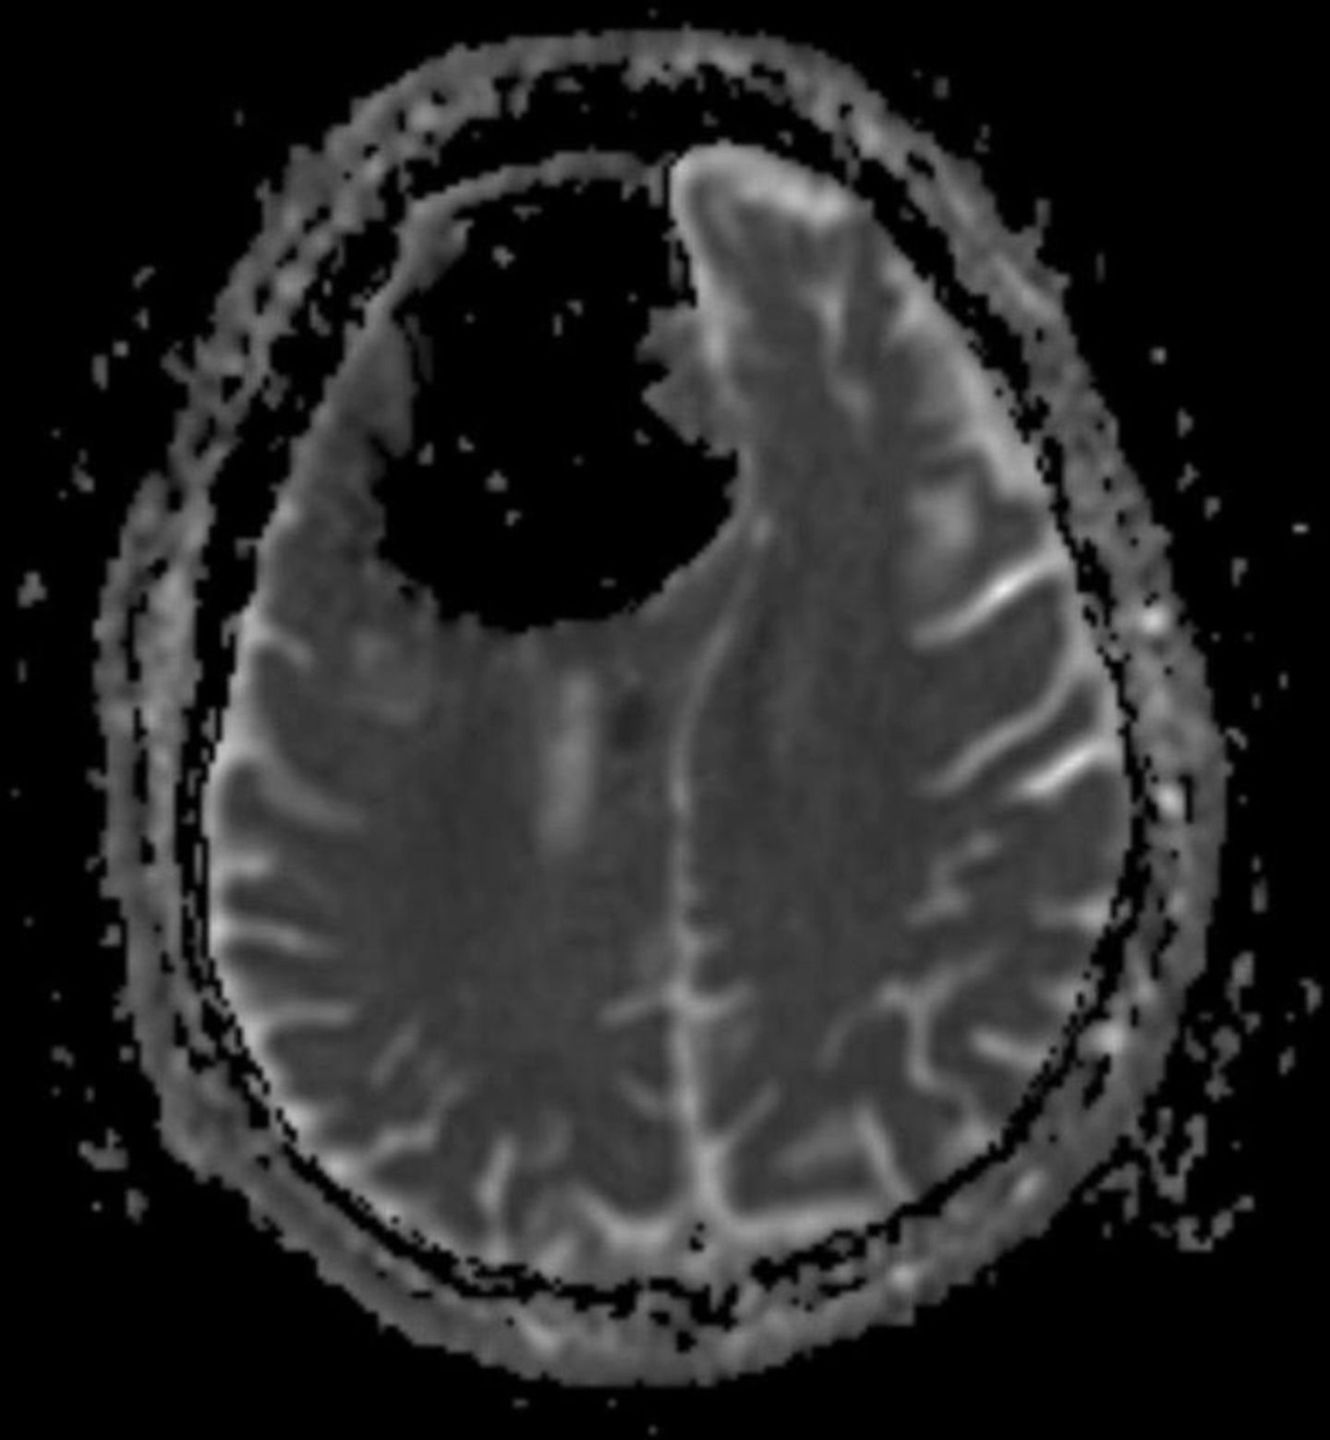

Na zdjęciach najlepiej widać, jak sporej części mózgu brakuje mężczyźnie

Widząc jego wyniki lekarze byli zaszokowani. Okazało się bowiem, że mężczyźnie brakuje sporej części mózgu. Zamiast tkanki mózgowej, lekarze dostrzeli (najprawdopodobniej) pęcherz powietrza o wielkości 9 cm. Na jego miejscu powinna znajdować się duża część prawego płata czołowego. Lekarze ogłosili to odkrycie w BMJ Case Reports.